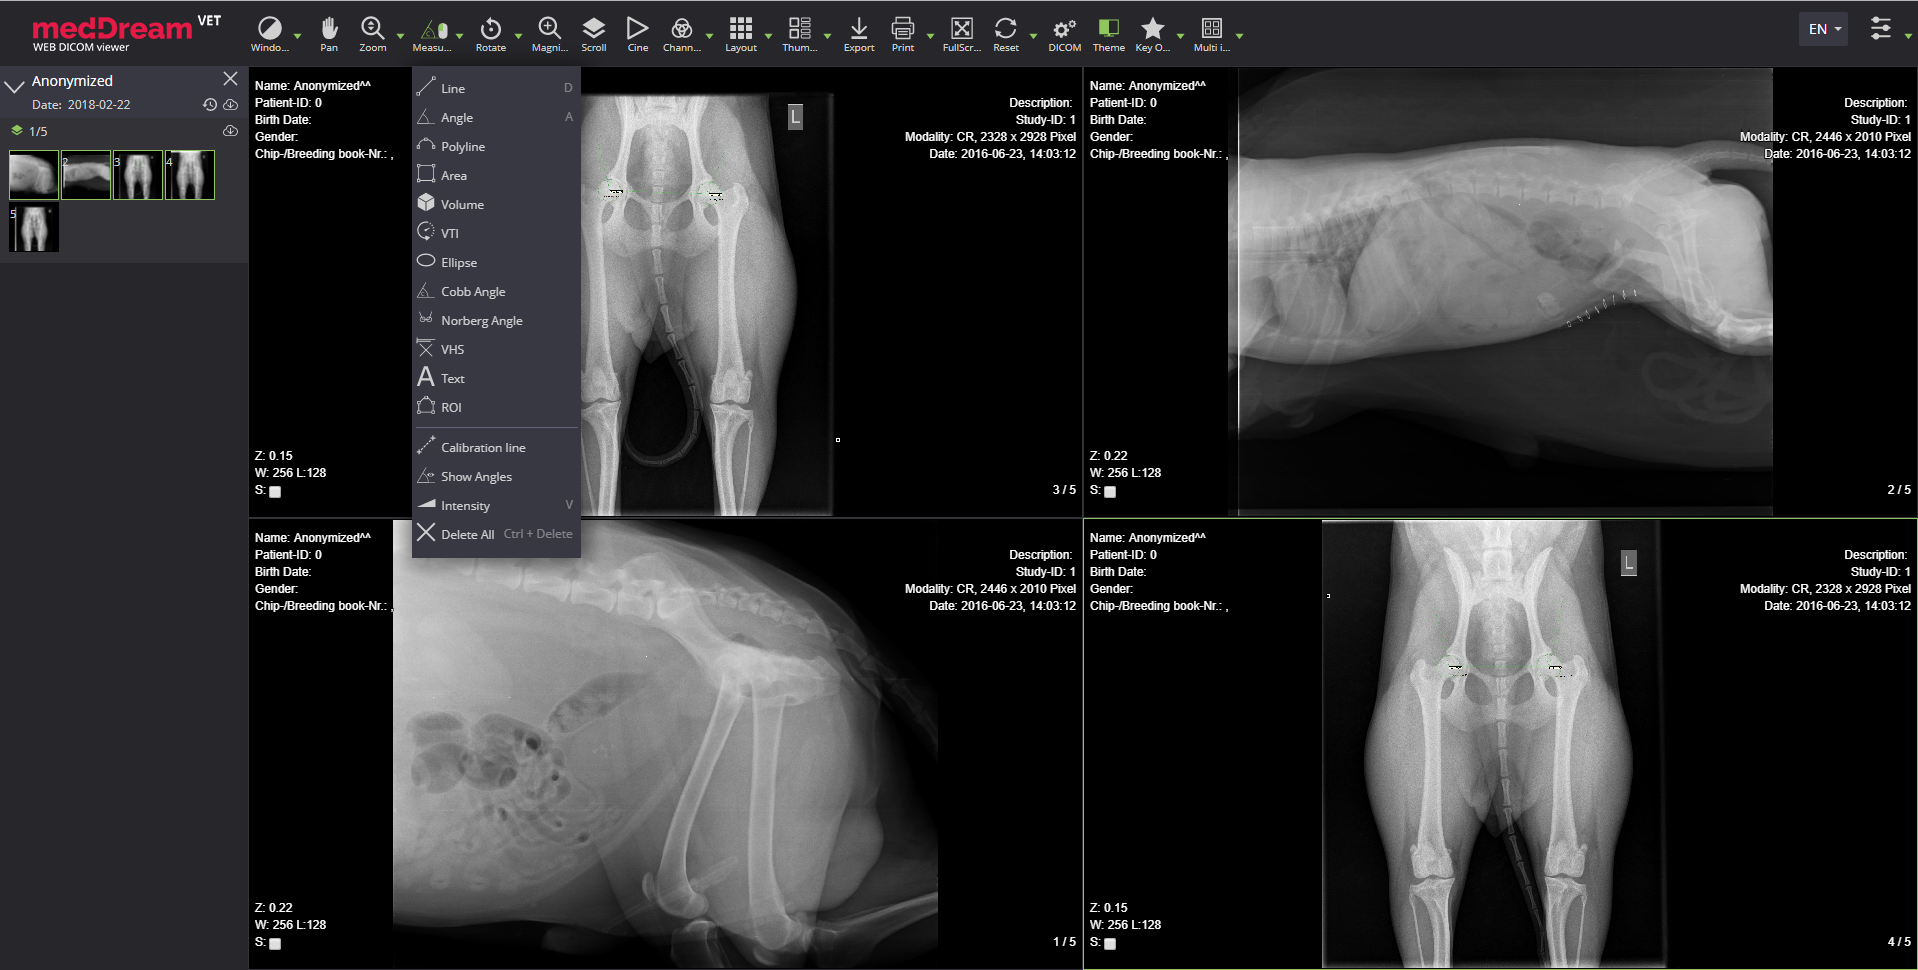

Meddream vet dicom viewer radiology measure

The MedDream VET DICOM Viewer has an extensive radiology tool for veterinary imaging set, which includes regular features such as:

• Window. Image window level manipulation using the mouse or selecting from a list of available presets;

• Pan. Moving the image within the image viewer, useful when image is larger than the viewer, after zooming for example;

• Zoom. Increase/decrease the image;

• Scroll. Scroll through the images of series by using mouse wheel, dragging vertically or with keyboard hot keys;

• Rotate/Flip. Rotate the image right/left, flip it horizontal/vertical with possibility to revert the image to original orientation;

• Magnifier. Magnify (enlarge) certain area of the image.

Measurements VHS and Norberg angle

The MedDream VET DICOM Viewer's specific measurements for veterinary field are:

• Line. Draw and measure the length of a line;

• Polyline. Draw and measure the length of a polyline;

• Area. Mark area of interest with a polyline and measure its area;

• Angle. Draw and measure an angle;

• Cobb angle. Draw and measure a Cobb angle;

• Show angles. Show all angles between intersecting lines;

• Norberg angle. Measure a Norberg angle to evaluate canine hip dysplasia;

• VHS. Measure Vertebral Heart Score/Scale to asses cardiac enlargement;

• Ellipse. Draw and measure an ellipse, which calculates standard deviation and mean values in Hounsfield units;

• Volume. Measure the volume of a 2D image. The 2D area is spun around a selected axis to form a 3D shape and the volume of the shape is then measured;

• Text. Possibility to write, view, edit or delete text;

• ROI. Mark and store ROI for study instance;

• Calibration line. Change the scale of measurement;

• Intensity. Measure Hounsfield units at a specific point of a CT study;

• Save annotation. Possibility to save and display annotations;

• Delete annotation. Possibility to delete all or selected annotations.